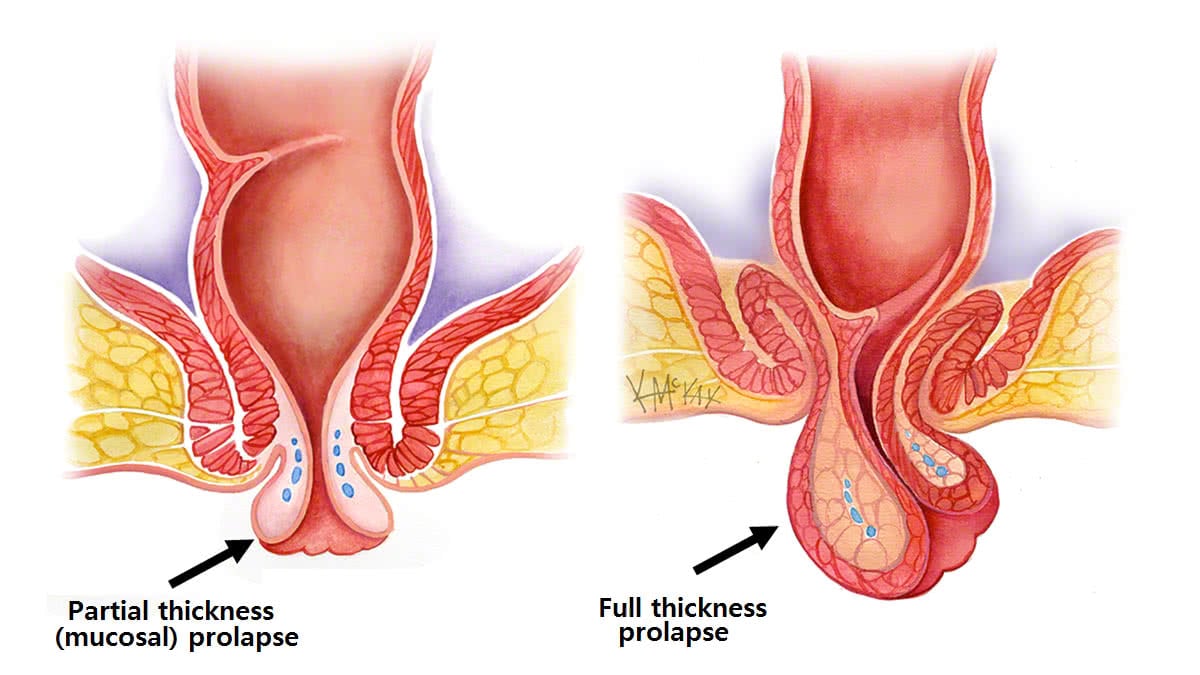

افتادگی راستروده : پرولاپس رکتوم زمانی اتفاق میافتد که بخشی از پایینترین بخش روده بزرگ، راست روده، به بیرون از منفذ عضلانی در انتهای دستگاه گوارش معروف به مقعد میلغزد. در حالی که پرولاپس رکتوم ممکن است باعث درد شود، به ندرت یک اورژانس پزشکی است.

اگر پرولاپس رکتوم دارید، ممکن است متوجه یک توده قرمز رنگ شوید که از مقعد بیرون میآید، اغلب در حین اجابت مزاج. این توده ممکن است به داخل مقعد برگردد، یا ممکن است همچنان دیده شود.